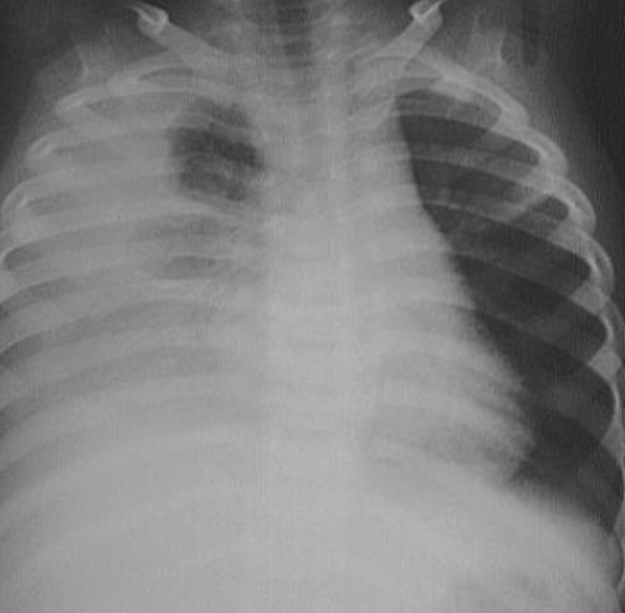

- AP chest film which shows opacification of the middle and lower zones of - (1 .the left lung. The upper border of the opacity is concave

- .This indicates pleural effusion (PE) - (2

- After inserting chest tube, pus was coming out. This means that the PE is - (3 .an Empyema

- .The cause of this empyema is most likely a Bacterial Pneumonia - (4

- The age of the patient is an 8 years which means that the most likely - (5 .organism is Streptococcus Pneumonae